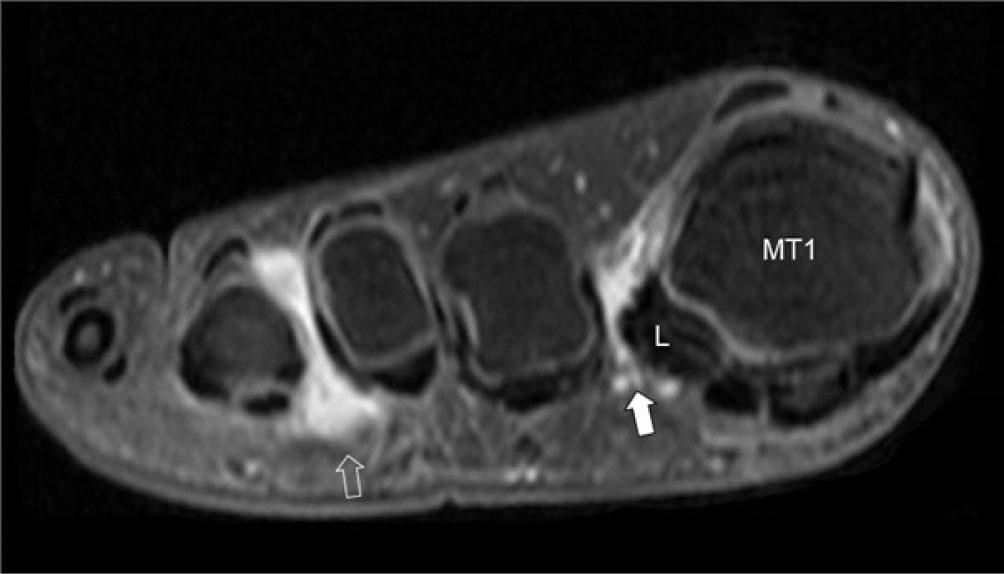

Fig. 17.

Coronal gadolinium-enhanced T1W FS MR image at the level of the MTP joints of a patient with early arthritis. There is enhancement of the intermetatarsal bursae in the 1st (arrow) and 3rd (open arrow) web spaces. The lateral sesamoid bone (L) and 1st metatarsal base (MT1) is rotated such that impingement between this sesamoid bone and the 2nd metatarsal bone may be leading to inflammation of the 1st intermetatarsal bursa